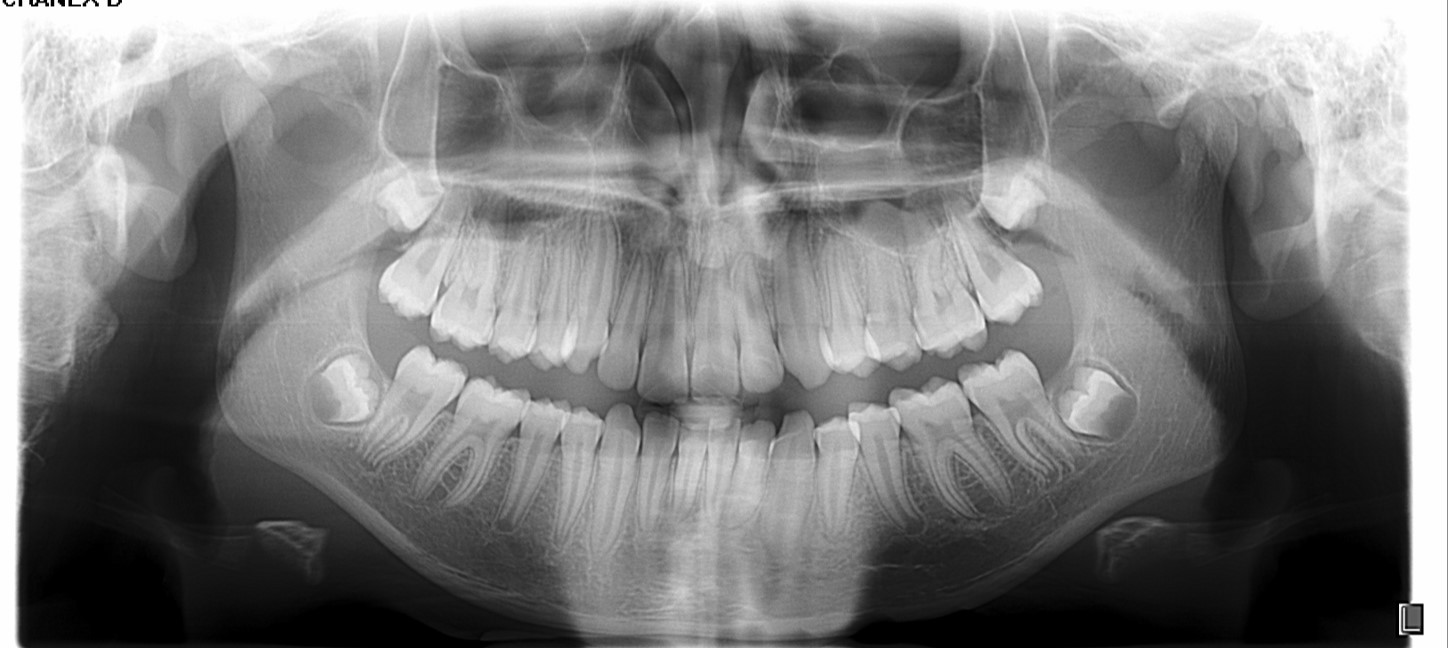

Chief complaint: We present the case of a 12-year-old female patient who came for an orthodontic evaluation, motivated by a family history of treatment. Clinical and radiographic analysis revealed a skeletal Class II malocclusion with molar and canine relationships also in Class II, moderate crowding in both arches, a deviation of the dental midline, and ectopic eruption of tooth 13. No functional issues with breathing or swallowing were observed, and oral health was generally good. A slight mandibular retrusion was noted in the soft tissue profile. A treatment plan was proposed using the Angel Aligner Pro system, aiming to correct dental misalignments and improve facial harmony through a minimally invasive, growth-adapted approach.

Clinical examination and diagnosis

- Woman ; 12/3 years

- Skeletal Class II

- Molar and canine Class II

- Upper and lower dentoalveolar compression

- Increased overjet and overbite

- Upper midline deviated 0,5 mm to the right

- Moderate upper and lower crowding

We approached the case by combining upper distalization using the A8 protocol with an asymmetric virtual jump. In this way, we solved the crowding without proinclining the incisors and improved the anteroposterior relationship through the use of elastics. In the lower arch, we carry out a development of the posterior sectors prior to the resolution of the crowding, in order to avoid roundtripping and excessive IPR of the incisors. To achieve an effective extrusion and distalization of 13, we combine the use of direct bonding button on vestibular of 13, with angelButton elastics mesial and distal to the canine. These mechanics help to ensure that the extrusion is real and that the aligner always remains adapted.